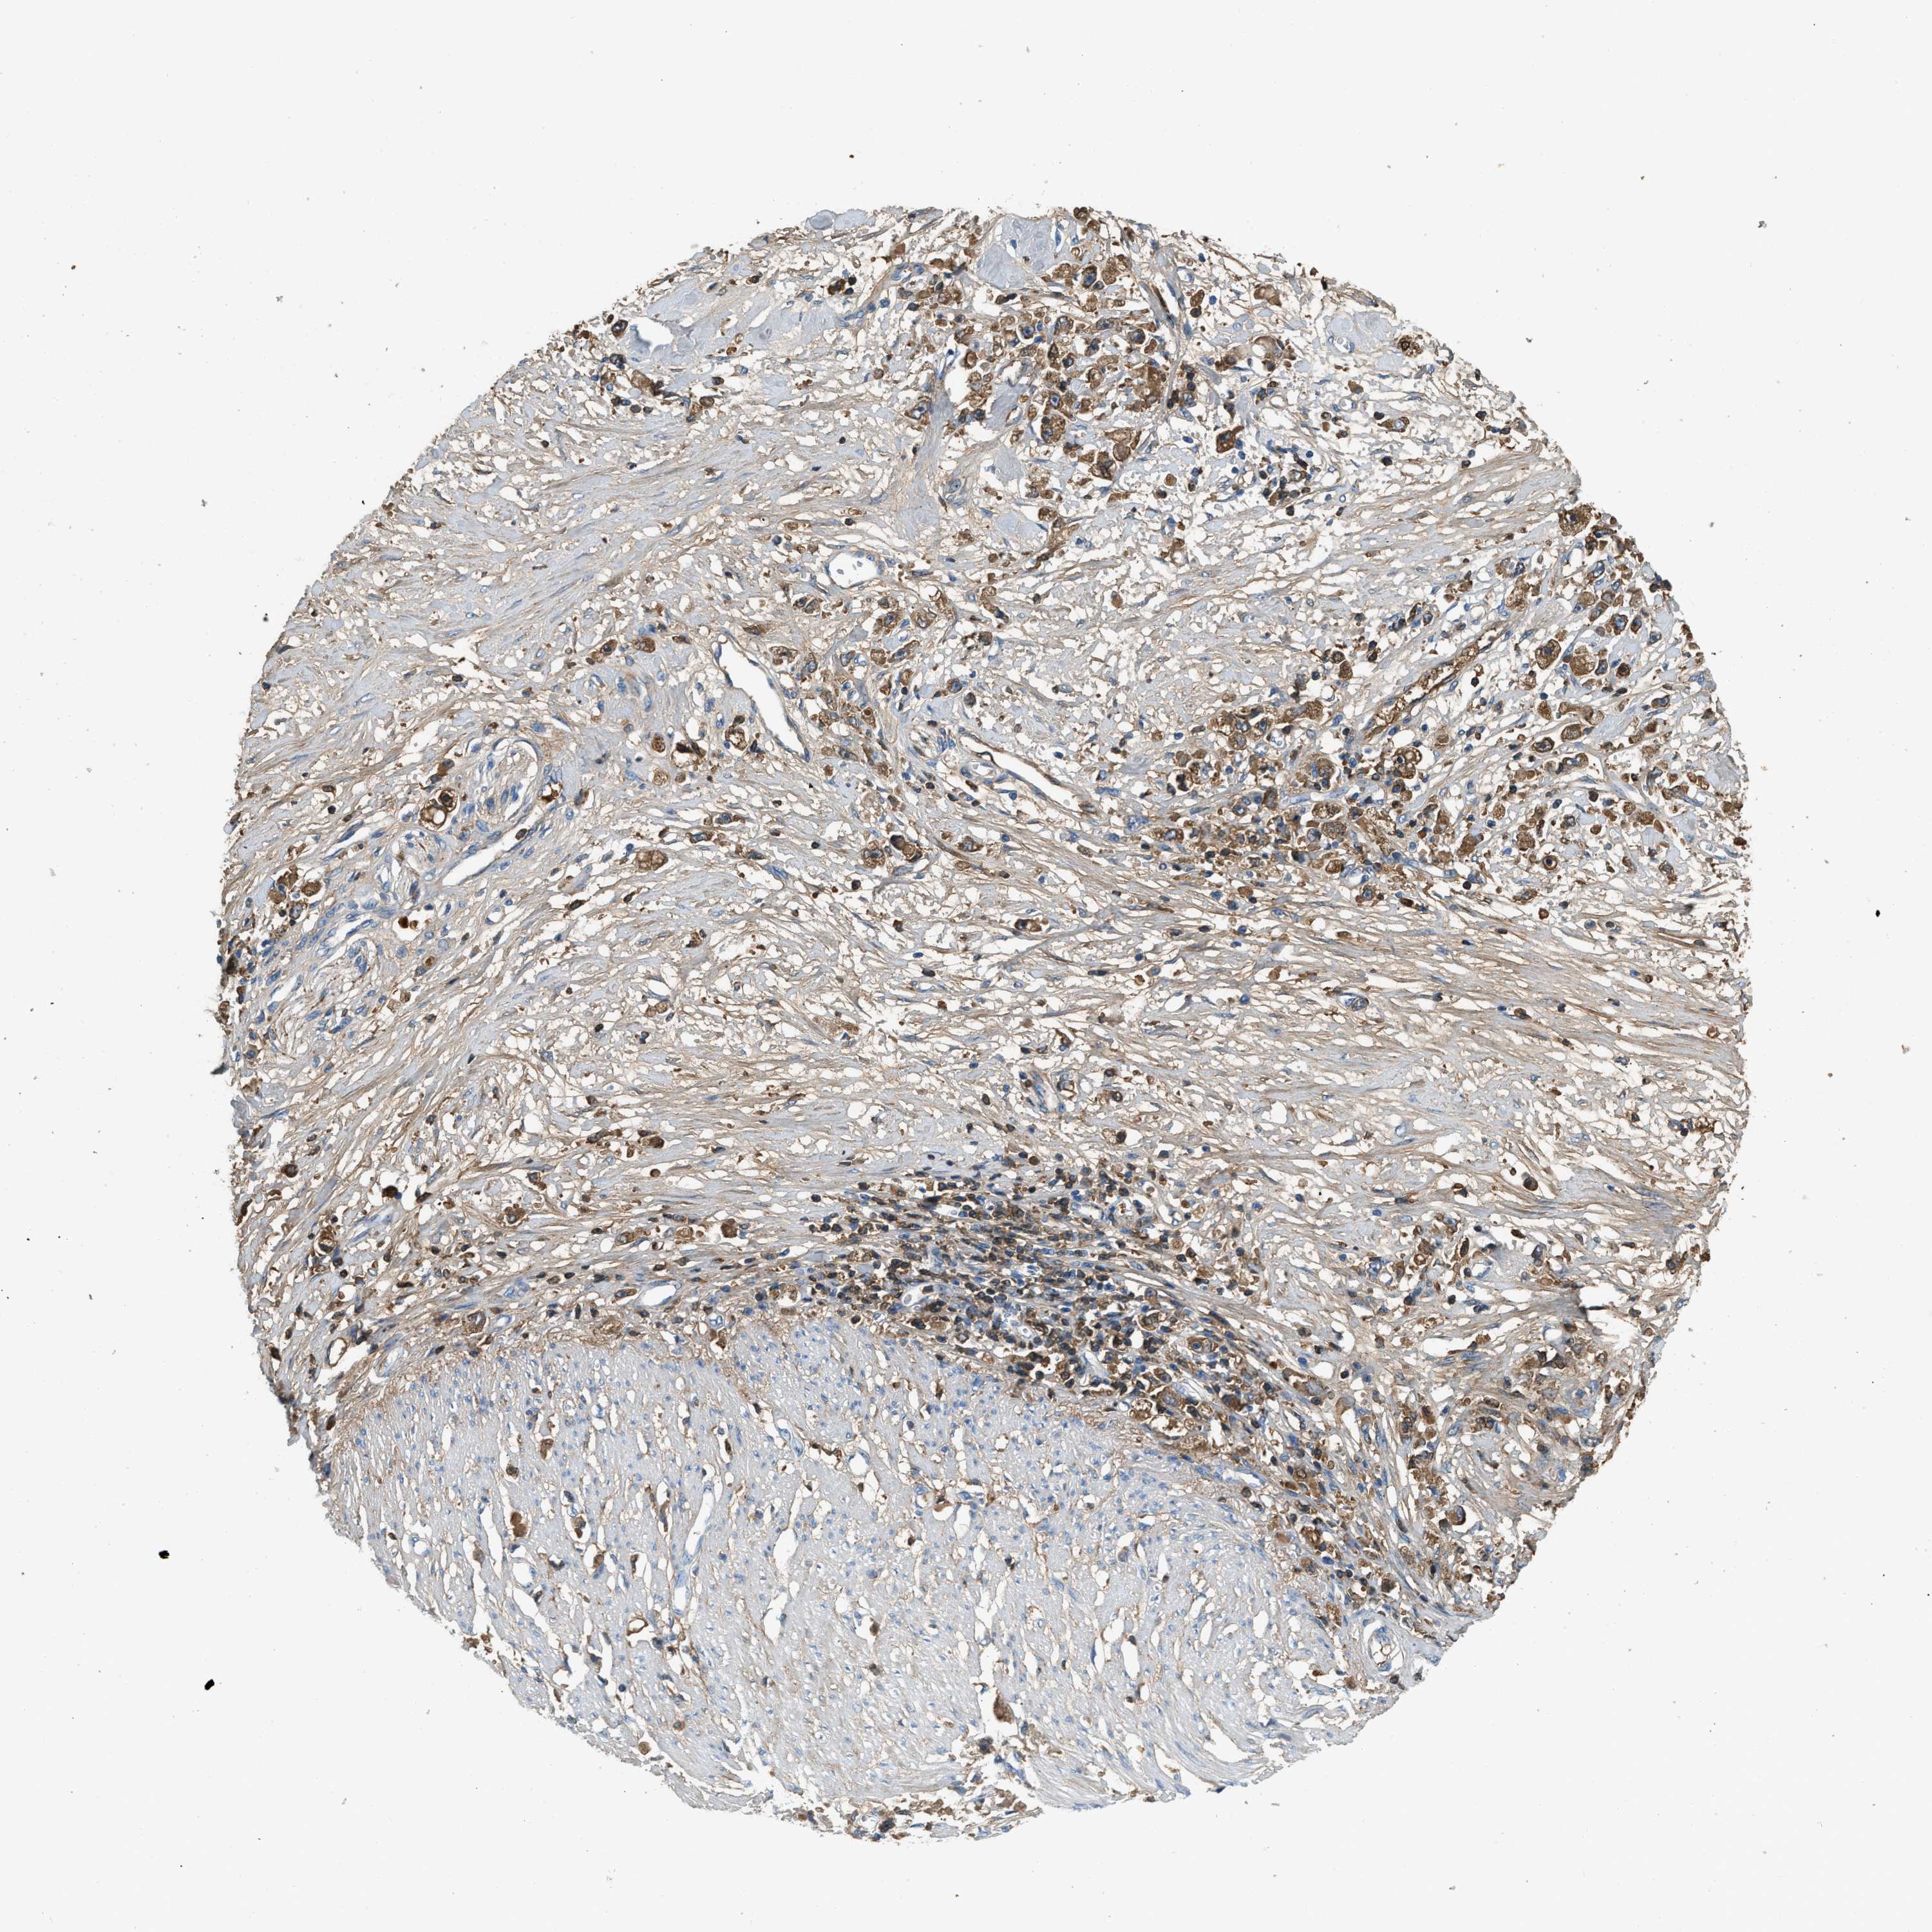

STOMACH CANCER - Protein expressioni

A mouse-over function shows sample information and annotation data. Click on an image to view it in a full screen mode. Samples can be filtered based on level of antibody staining by selecting one or several of the following categories: high, medium, low and not detected. The assay and annotation is described here.

Note that samples used for immunohistochemistry by the Human Protein Atlas do not correspond to samples in the TCGA dataset.

Antibody stainingi

Antibody staining in the annotated cell types in the current human tissue is reported as not detected, low, medium, or high, based on conventional immunohistochemistry profiling in selected tissues. This score is based on the combination of the staining intensity and fraction of stained cells.

Each image is clickable and will lead to virtual microscopy that enables deeper exploration of all samples and also displays staining intensity scores, fraction scores and subcellular localization as well as patient and tissue information for each sample.

Antibody HPA023918

Antibody CAB018625

Staining

High

Medium

Low

Not detected

Intensity

Strong

Moderate

Weak

Negative

Quantity

>75%

75%-25%

<25%

None

Location

Nuclear

Cytoplasmic/membranous

Cytoplasmic/membranous,nuclear

Adenocarcinoma, NOS